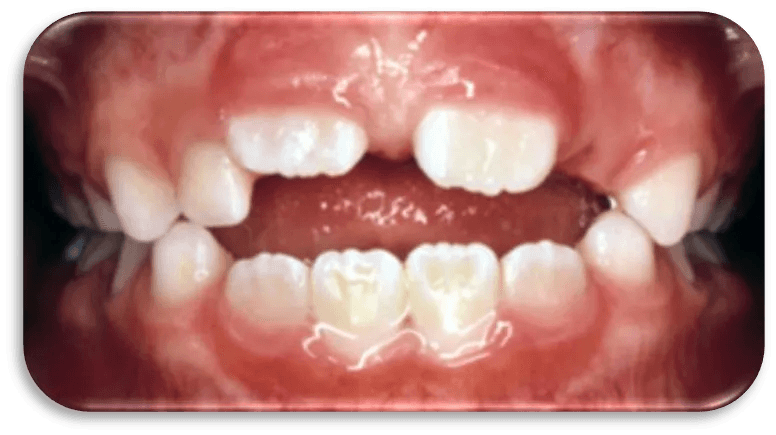

Result of Pacifier and Prolonged Nipple Bottle Use and Resulting Finger Sucking

Crowded teeth

Underdeveloped Dental Arches

Overjet / Open Bite

Cross Bite